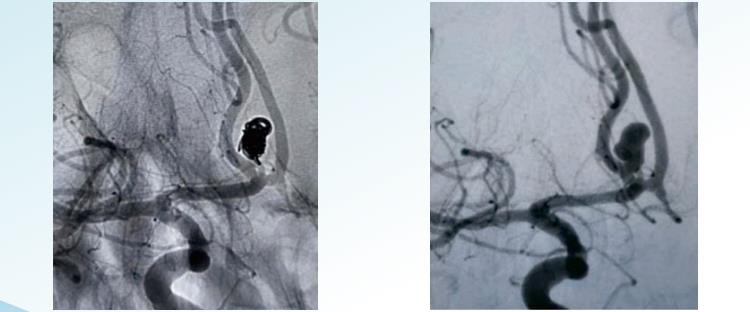

Ta'mirlashTMolinadigan anevrizma o'rash tizimi 1 dan 22 m gacha diametrli endovaskulyar embolizatsiya uchun tasodifiy, spiral va 3D ajratiladigan variantlarni taklif qiladi. U anevrizmalarni ramkadan oxirigacha embolizatsiya qilish uchun mo'ljallangan va konsentrik anevrizmani to'ldirishga erishish uchun maxsus shakllangan spirallarni va yuqori qadoqlash zichligiga erishish uchun katta hajmli spirallarni o'z ichiga oladi. Tasodifiy o'rash anevrizmani o'rash texnikasining eng oddiy va eng qadimgi shaklidir. Bu anevrizmaga bitta spiral yoki bir guruh sariqlarni kiritishni o'z ichiga oladi. Bobinlar odatda platinadan tayyorlanadi va sumkada bo'shliqlar yoki bo'shliqlar paydo bo'lishining oldini olish uchun ingichka va mahkam o'ralgan. Spiralli o'rash o'z atrofida spiral tarzda o'ralgan, prujinaga o'xshash strukturani tashkil etuvchi uzunroq, ingichka simdan foydalanishni o'z ichiga oladi. Sim anevrizmaga to'g'rilangan shaklda kiritiladi va ichkariga kirgandan so'ng, anevrizma qopini to'ldirish uchun o'ralgan va kengayishiga ruxsat beriladi. Spiral spirallar tasodifiy bobinlarga qaraganda kengroq va zichroq o'ralgan bo'lib, anevrizmaning yaxshi yopilishini ta'minlaydi. 3D spiral anevrizmaning aniq uch o'lchovli modelini yaratadigan kompyuterlashtirilgan tasvirlash jarayoni yordamida tayyorlangan maxsus mo'ljallangan spiraldan foydalanishni o'z ichiga oladi. Bobin anevrizmaning aniq hajmi va shakliga mos keladigan tarzda ishlab chiqariladi. Ushbu turdagi spiral anevrizma qopiga mahkam o'rnashib olish uchun mo'ljallangan bo'lib, mukammal oklyuziyani ta'minlaydi va asoratlar xavfini kamaytiradi. 3D spirallar ayniqsa erishish qiyin bo'lgan yoki mo'rt qon tomirlaridagi anevrizmalarni davolashda samarali.

5. Ramkani mahkam bog'lang, bir xilda to'ldiring va anevrizma ichidagi bo'shliqlarni qidirib tugating.